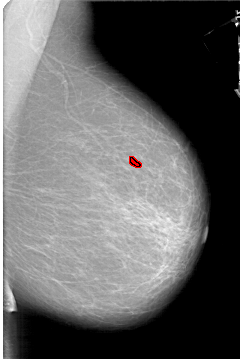

A_1333_1.RIGHT_MLO

RIGHT_MLO LINES 6451 PIXELS_PER_LINE 4306 BITS_PER_PIXEL 12 RESOLUTION 43.5 OVERLAY

FILE: A_1333_1.RIGHT_MLO.OVERLAY

TOTAL_ABNORMALITIES 1

ABNORMALITY 1

LESION_TYPE CALCIFICATION TYPE PLEOMORPHIC DISTRIBUTION CLUSTERED

ASSESSMENT 4

SUBTLETY 2

PATHOLOGY BENIGN

TOTAL_OUTLINES 1

BOUNDARY